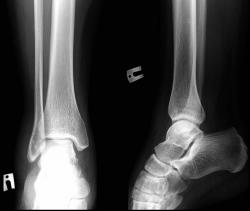

Отличные, высокоструктурные снимки - честь Вам и Вашим помощникам - лаборантам. Сначала тоже сильно засомневался, ибо линия перелома (смещения то нет) "накладывается" на задний контур м/берцовой кости, но нижний снимок убедил, что перелом "задней" лодыжки.

Валентин Львович, я ни стал мучить пациента и делать в косой проекции, но на будущее я обязательно учту, сопоставив кническую и рентген-картину(если внимательно поглядеть то линия перелома не совсем наклалывается на край м/берцовой кости, а так же четко визуализируемую структуру костных балок, которые четко видно на цифре), было выставлено заключение о переломе.

Ребяты! Всё тут видно. Но можно лучше. Ставим в браузере масштаб не 100%, а 200% или 300% и видим (даже без очков!) – линия перелома б. берцовой позади проекции контура м. берцовой и направления их книзу расходятся.

По представленному случаю. Имеется изолированный перелом заднего края большеберцовой кости без смещения костных отломков. Кстати, редко встречаются изолированные. Чаще в сочетании с переломами лодыжек, вывихом таранной кости.